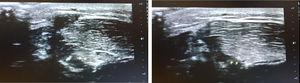

Presentamos el caso de un adolescente de 15 años que desde hace 2 meses presenta la aparición de bultomas en las extremidades inferiores de manera progresiva. Estas lesiones le generan dolor durante el ejercicio, y le condiciona el mismo. Se trata de un adolescente sano, sin antecedentes personales de interés y deportista. La exploración en reposo revela 3 bultomas en el miembro inferior derecho (fig. 1) y 2 en el izquierdo, de consistencia blanda, no dolorosas, no eritematosas, ni calientes, en zona tibial anterior. Durante la contracción muscular, dichos bultomas desaparecen (fig. 2). Se realiza ecografía en la que se objetiva defecto de la fascia muscular, sin hallazgos compatibles con lipoma ni lesiones vasculares (fig. 3) (video). Se realiza tratamiento conservador con reposo deportivo y se deriva a traumatología.